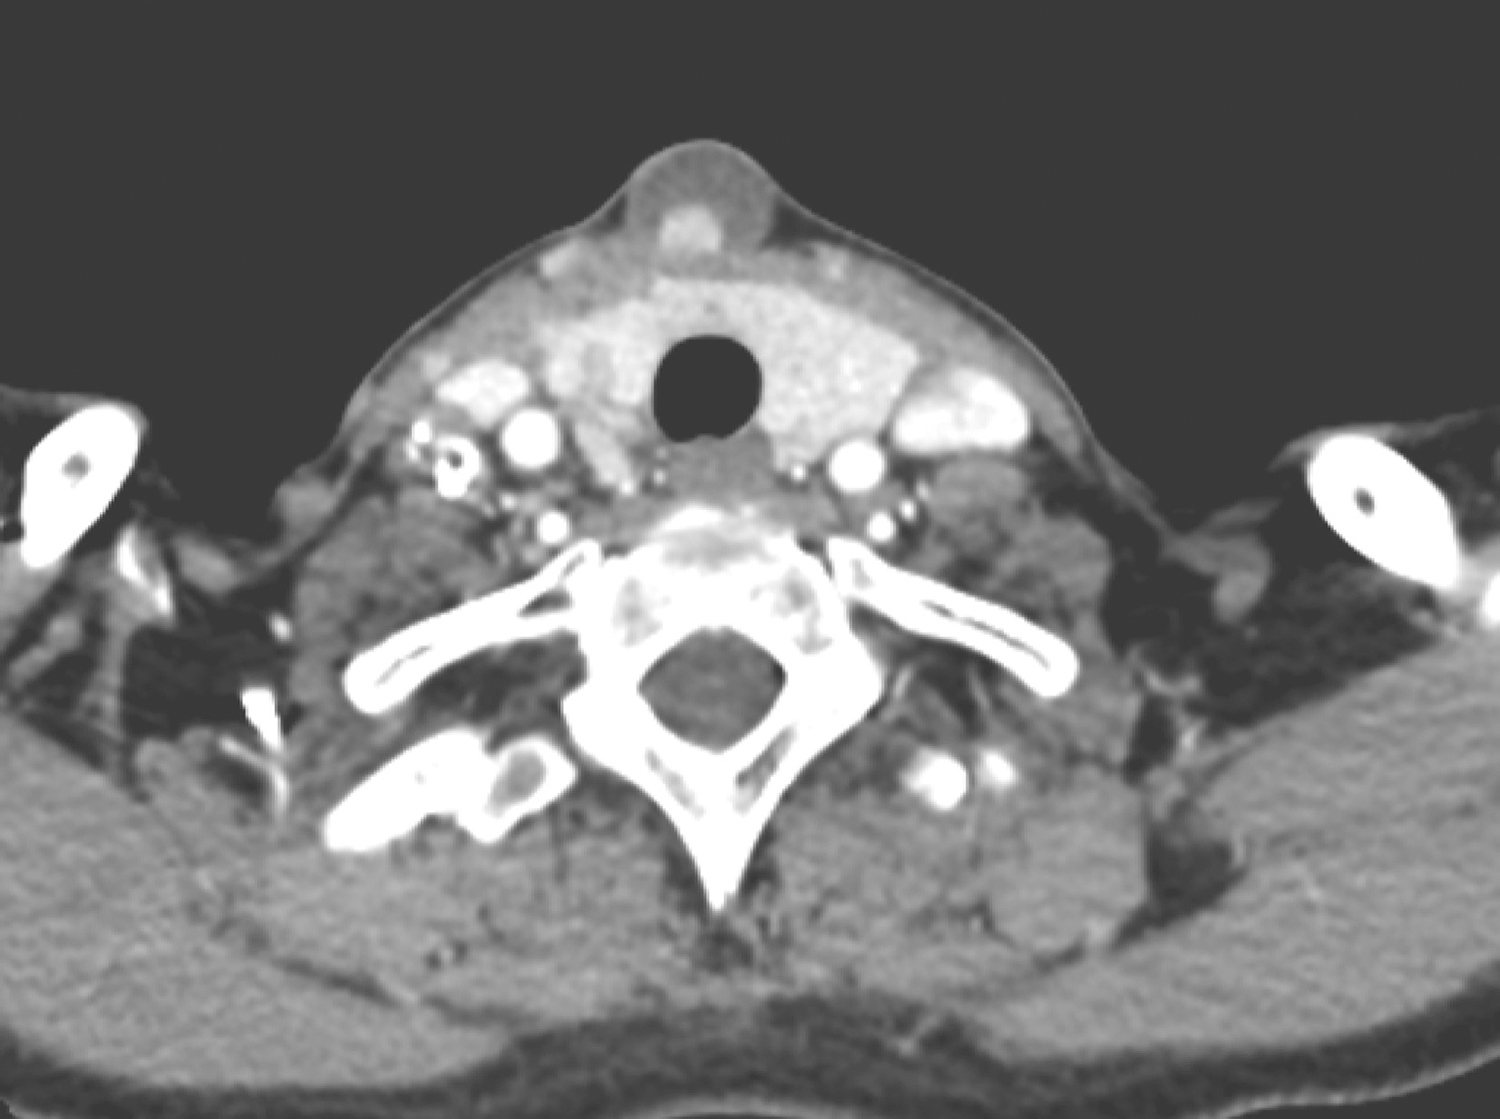

2.2017年8月8日颈胸部增强CT

颈前正中可见一直径1.9cm大小的类圆形低密度影,边界清楚,其内可见一直径0.8cm大小的强化结节影(图3);甲状腺右叶见斑片状低密度影,边界不清楚,其内见斑片状、斑点状钙化密度影;甲状腺左叶见斑片状低密度影;右颈见多发结节状稍高密度影,边缘见环形钙化影,轻度强化(图4)。

图3 颈部增强CT示颈前正中类圆形低密度影内的强化结节影

图4 颈部增强CT示右颈多发结节状稍高密度影伴钙化